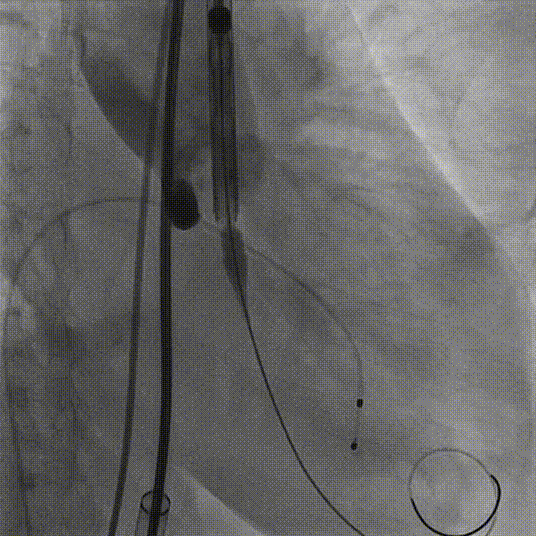

4.TaurusElite AV23号瓣膜定位及释放。瓣膜初始定位0位,开花后120次起搏,释放到工作位后造影显示锚定充足,位置良好,冠脉未见遮挡,继续缓慢旋转手柄,轻推输送器,瓣膜逐一脱钩,顺利释放。

瓣膜初始定位

瓣膜释放过程

工作位造影

瓣膜脱钩

5.释放后多体位观察造影,提示瓣膜位置良好,展开良好,双侧冠脉未见遮挡,微量瓣周漏。